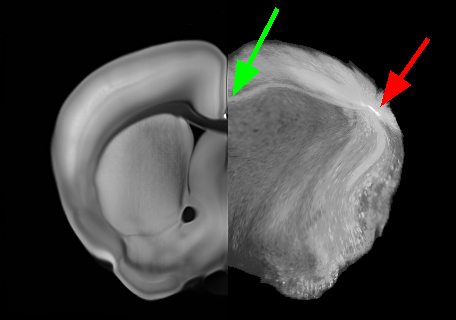

For registration, each CLARITY volume I0subscript𝐼0I_{0} was downloaded from the NeuroData cluster. They were resampled to a 50 μm𝜇𝑚\mu m resolution and registered to ARA atlas image J1subscript𝐽1J_{1} with 12-parameter affine alignment under MI matching. Deformable registration was then done with MI-LDDMM as implemented in ndreg. A cascaded-α𝛼\alpha approach was adopted in which a smoother registration with α=0.05𝛼0.05\alpha=0.05 was followed by registrations at α=0.02𝛼0.02\alpha=0.02 and α=0.01𝛼0.01\alpha=0.01 to refine the results (Fig. 2). Both ARA-aligned CLARITY volumes and CLARITY-aligned ARA annotations were uploaded to the NeuroData cluster. This allowed us to visualize ARA annotations overlaid on the terabyte-scale CLARITY images (Fig 1). Deformable registration was done with SSD-LDDMM and Mask-LDDMM to demonstrate the advantages of MI-LDDMM. For validation MI-LDDMM was also compared to SyN ANTs [1] with MI cost and σ=1.0𝜎1.0\sigma=1.0 mm Gaussian regularization (Fig. 3).

Refer to caption

(d) SyN

Figure 3: Comparison of SSD-LDDMM (3(a)), Mask-LDDMM (3(b)), MI-LDDMM (3(c)) and SyN ANTs (3(d)) registration of CLARITY volume. Panes (3(a)-3(d)) have an ARA coronal slice on the left juxtaposed to the corresponding aligned CLARITY slice on the right. Green arrows point out that the corpus callosum is misaligned by SSD-LDDMM but aligned correctly by MI matching. Red arrows show that SSD-LDDMM distorts bright regions. Fiducial landmarks were manually placed in the corpus callosum, and midbrain of the acquired volumes. Pane (3(e)) compares mean errors between the deformed CLARITY and ARA landmarks after registration.